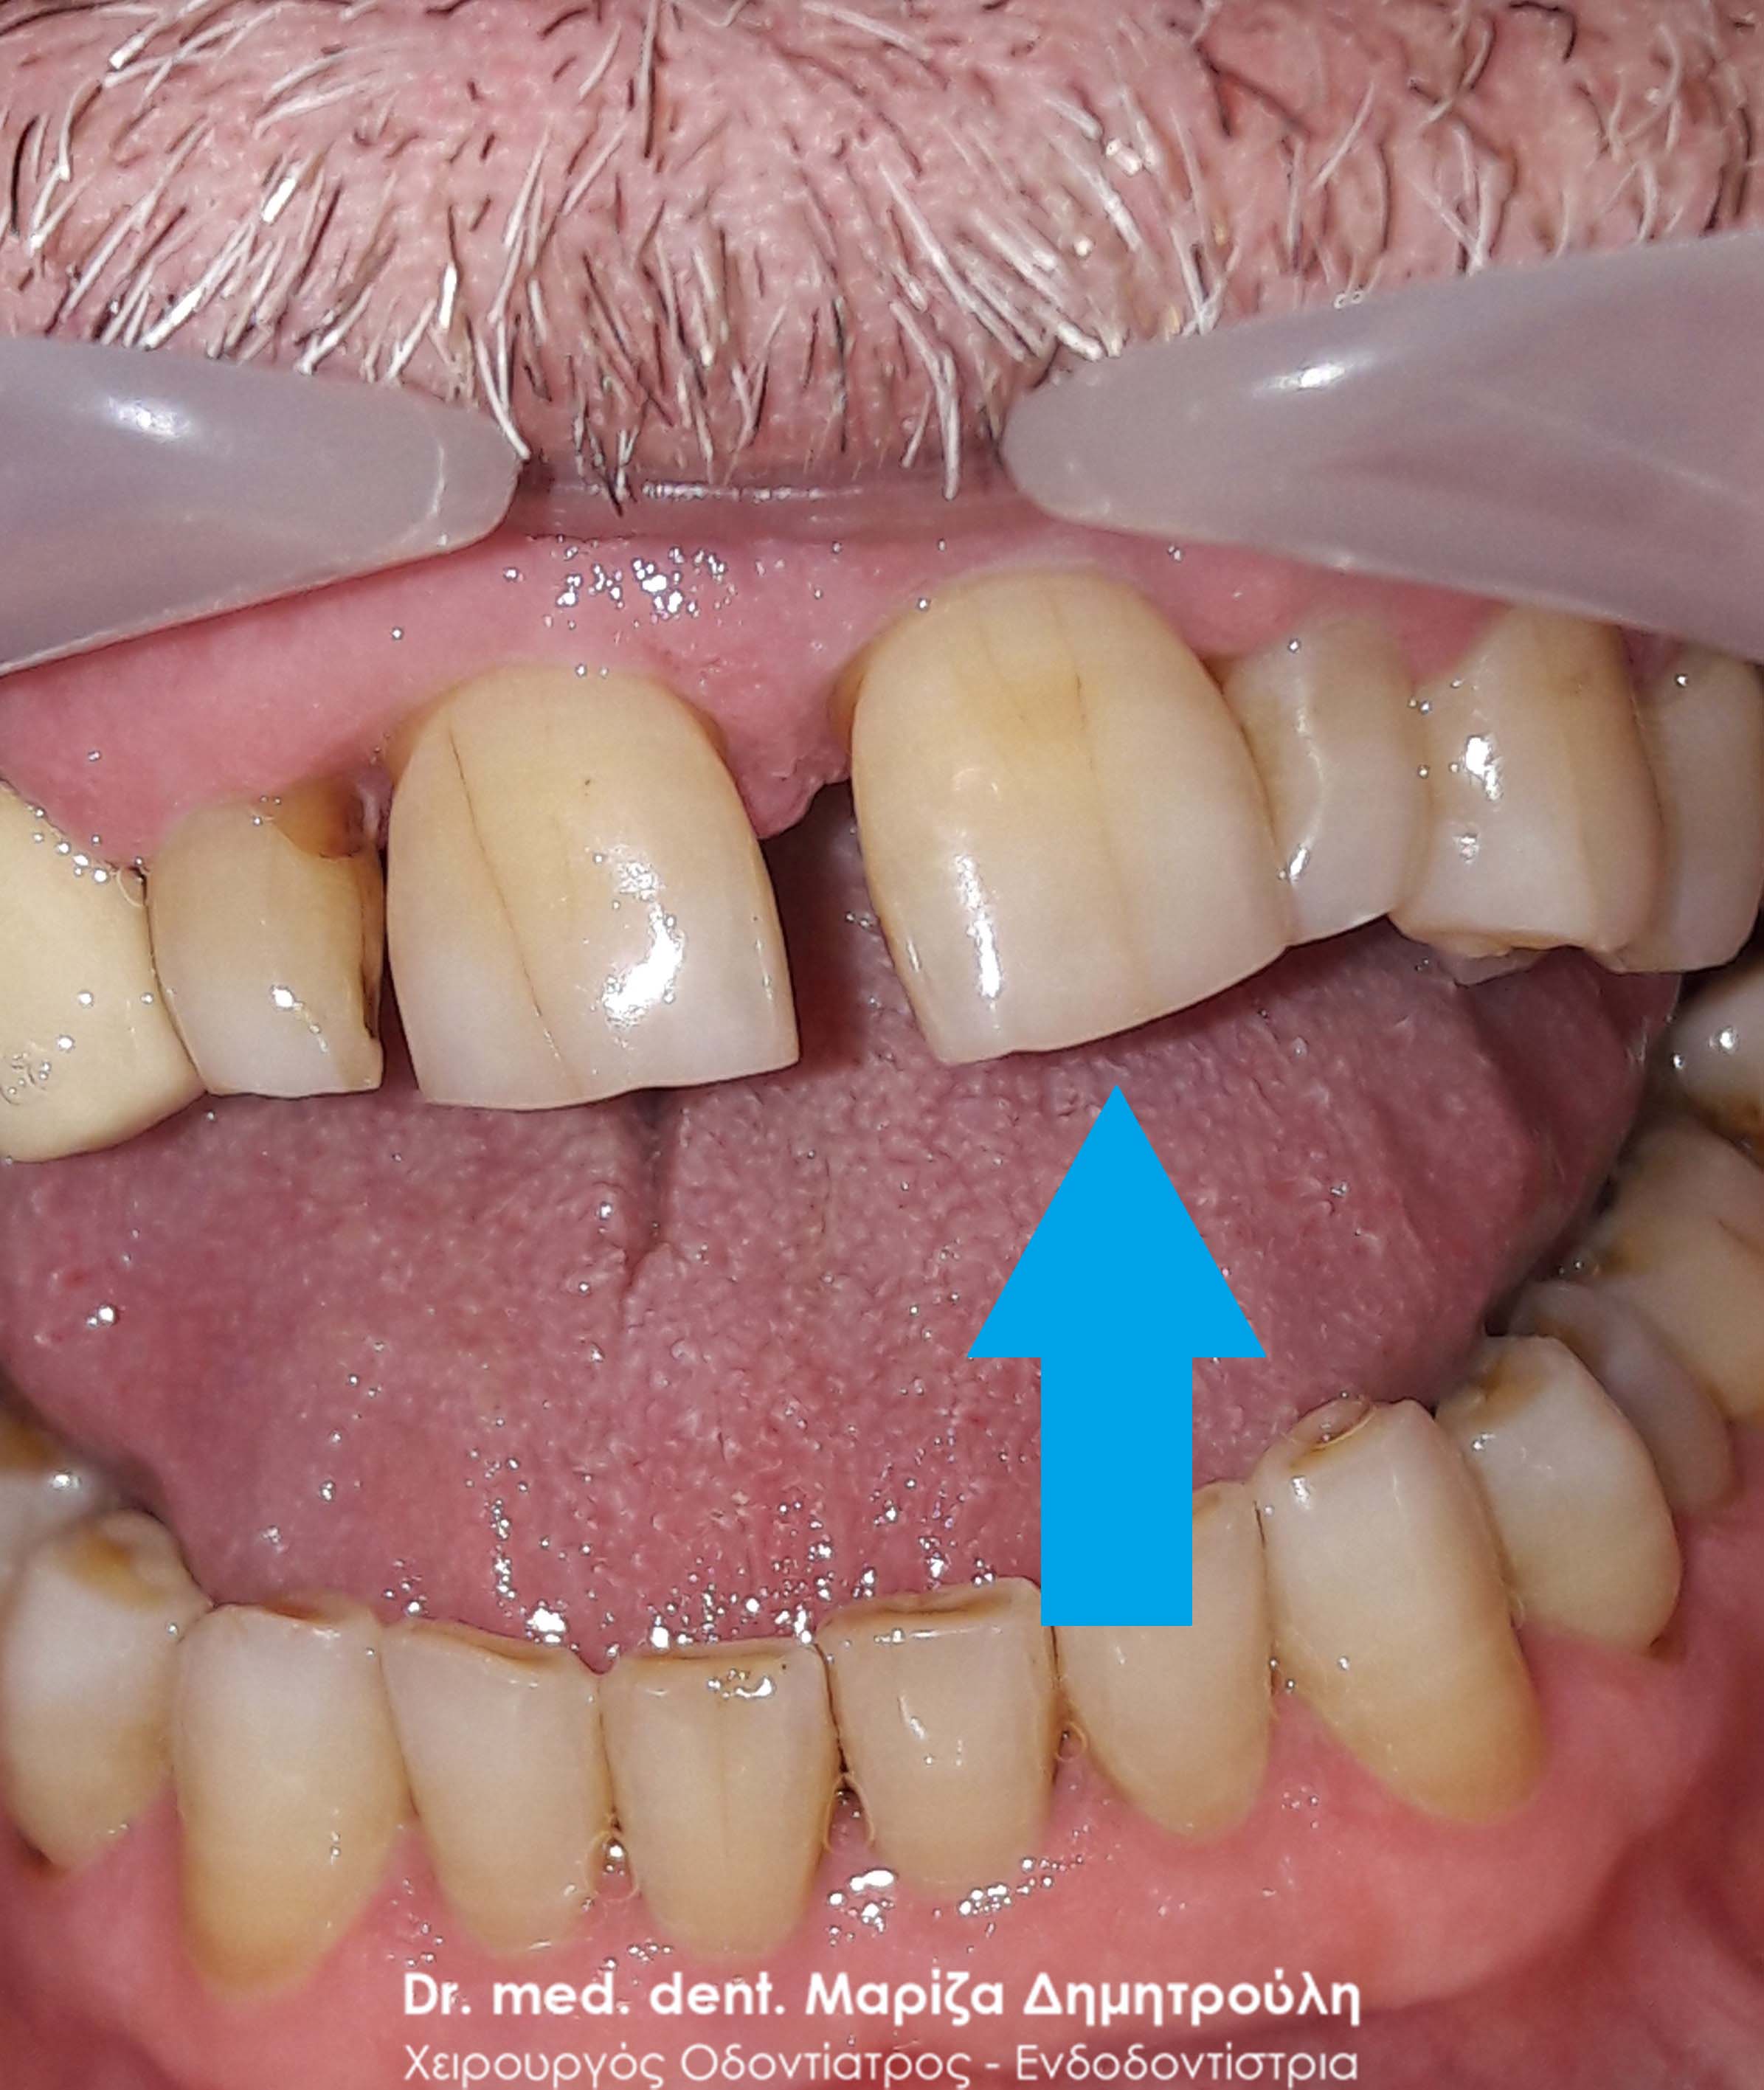

Ο ασθενής είχε για χρόνια μία πρόσθια νωδότητα στην κάτω γνάθο, την οποία αποφάσισε να αντικαταστήσει με προσθετική εργασία γιατί δεν αγαπούσε τα εμφυτεύματα. Μετά τις απαραίτητες εργασίες λήφθηκαν αποτυπώματα και κατασκευάστηκε ολοκεραμική γέφυρα, η οποία κάλυψε άριστα τόσο λειτουργικά όσο και αισθητικά το προϋπάρχον κενό.

Ο ασθενής είναι πολύ χαρούμενος με τα νέα του δόντια.

ΠΡΙΝ

ΜΕΤΑ